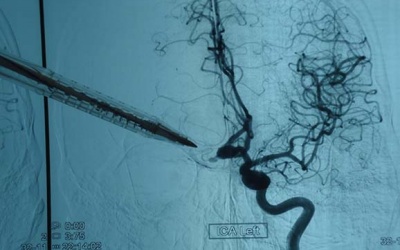

Cháu N.Đ.K (trú tại Hải Phòng) là trẻ sơ sinh nhỏ nhất ở Việt Nam mắc bệnh não úng thủy và được cứu sống bằng kỹ thuật vi phẩu thần kinh tại Bệnh viện Nhi Trung ương.